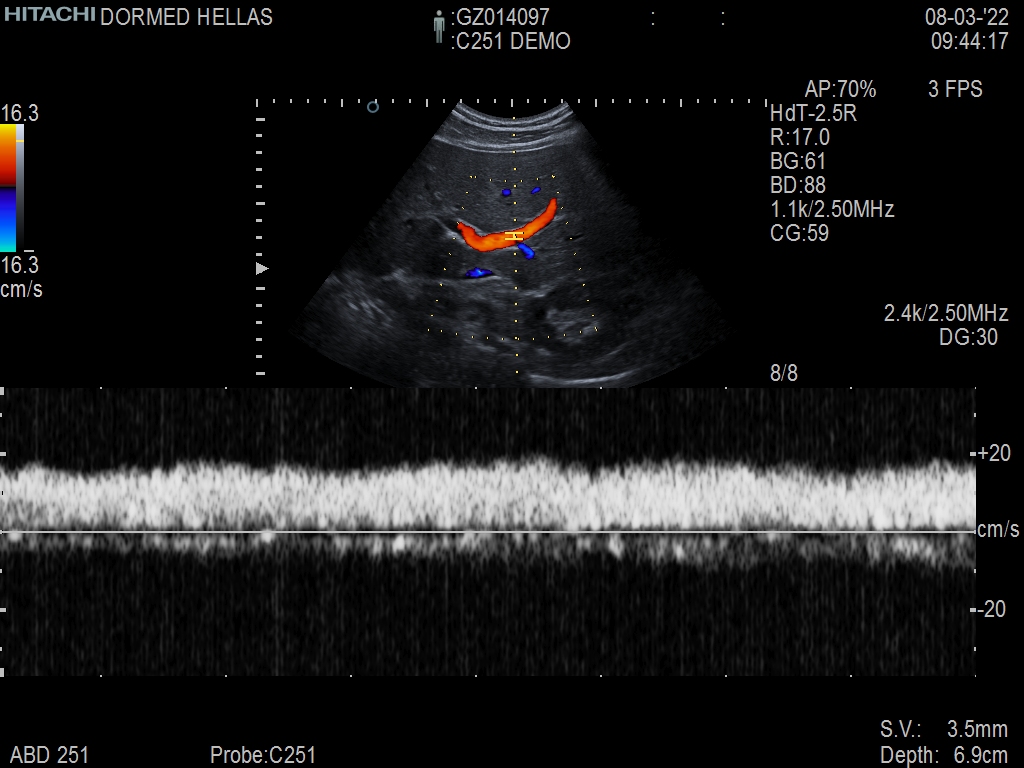

Hitachi C251 Ref Abdominal Convex – ARIETTA

ARIETTA Convex C251 Abdominal

Hitachi C251 Abdominal Convex – ARIETTA

Hitachi C251 Abdominal Convex – ARIETTA for Abdominal and Women’s Health

| Radiology functions | Contrast Harmonic Imaging (CHI), Elastography (RTE), RT Sonography (RVS) |